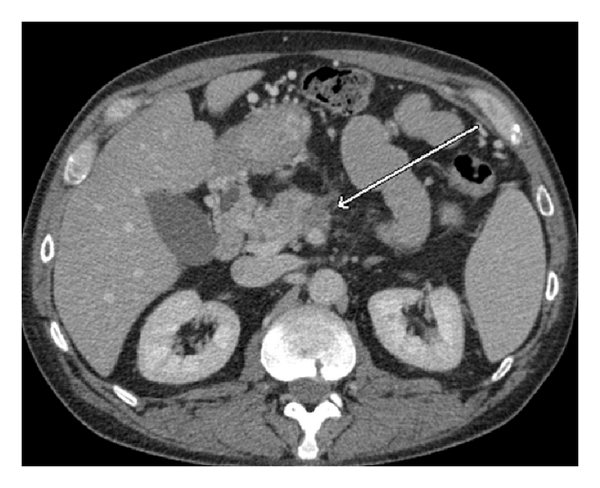

As Figures 1–5 demonstrate, the immediate postablation bed and zone are invariably larger than the original ablated tumor. We remain descriptive because the entire bed was extremely difficult to measure owing to the amorphous, irregular nature of the ablation. Moreover, the ablated tissue is not within an encapsulated organ; therefore, the ablation zone does not have defined borders as seen after, for instance, liver ablation. Four patients that showed continued stable disease are highlighted in Figures 1 through 4. An amorphous, hypoattenuating region with irregular shape persisted in subsequent CT scans in all patients with “stable disease.” Moreover, the ablation zone was typically smaller (due to decreased edema, hyperemia, and granulation tissue) than the immediate postablation bed in the following months and remained stable provided there was no recurrence. Imaging findings demonstrating recurrence are shown in Figure 5. Along with persistent irregular shape the ablation zone showed increased tumor bulk and extension as well as new mass effect (new narrowing of a blood vessel). Enhancement of the ablative bed was variable and often showed increased enhancement in the three-month and longer follow-up images. This was felt to be related to development of granulation tissue and fibrosis.

In our study, we found that the postablation bed is larger in volume than the initial mass. This is expected because it contains the tumor and the ablative margin. The postablation bed and zone appear irregular, amorphous, and hazy without margins or true boundaries. The ablation zone may decrease in size from the initial post-op bed to the initial surveillance study as the surrounding edema/fluid and inflammation resolve revealing the true ablation zone; however, as mentioned above, since there have been reports of an ongoing apoptotic process that persists up to 6–8 weeks after ablation, it will not be unusual to see some increase in volume in surveillance [19, 20]. Therefore, size is considered secondary in the CT evaluation for this reason and because the postablative bed/zone has poorly defined margins, making objective imaging assessment (size, attenuation) cumbersome. This may undoubtedly affect the accuracy and reproducibility of the measurement. Nonetheless, any increase in volume after stabilization of the postablation zone is considered worrisome for recurrence (Figure 5).

Other clues that may suggest recurrence are any new encasement or narrowing of adjacent vessels or any subjective extension of soft tissue outside the boundaries of the previously established baseline ablation zone. However, in patients that have undergone prior radiation therapy or undergo post-IRE radiation therapy, persistent isolated narrowing (without other worrisome findings) is not always recurrence and must be followed with serial imaging, clinical evaluation, and CA19-9 serum tumor markers. Vessels within and adjacent to the ablation bed may show narrowing immediately after the procedure, but this should resolve or at least remain stable in subsequent studies. Often, if narrowing of a vessel is seen with the index tumor it will often persist after ablation. For equivocal cases, PET/CT may play a role in differentiating postablative changes from recurrence [25].